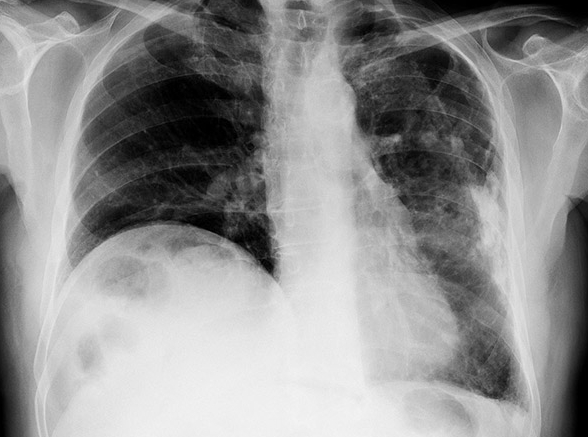

질병청에 따르면 국가건강검진에서 매년 약 1만2천명의 폐결핵 의심자가 나오지만 이 중 57%만 결핵 확진검사를 받는 것으로 나타났습니다. 이에 내년부터는 국가건강검진 대상자부터 검사비가 지원되며 검사는 각급 의료기관에서 받을 수 있습니다.

2주 이상의 기침·가래·발열·수면 중 식은땀 등 결핵 의심증상이 있거나 폐결핵 의심 소견을 받았다면 질병청 콜센터(☎1339)나 관할 보건소에 문의해 안전하게 진단 검사를 받고, 확진 환자는 처방에 따라 약을 복용해야 합니다.